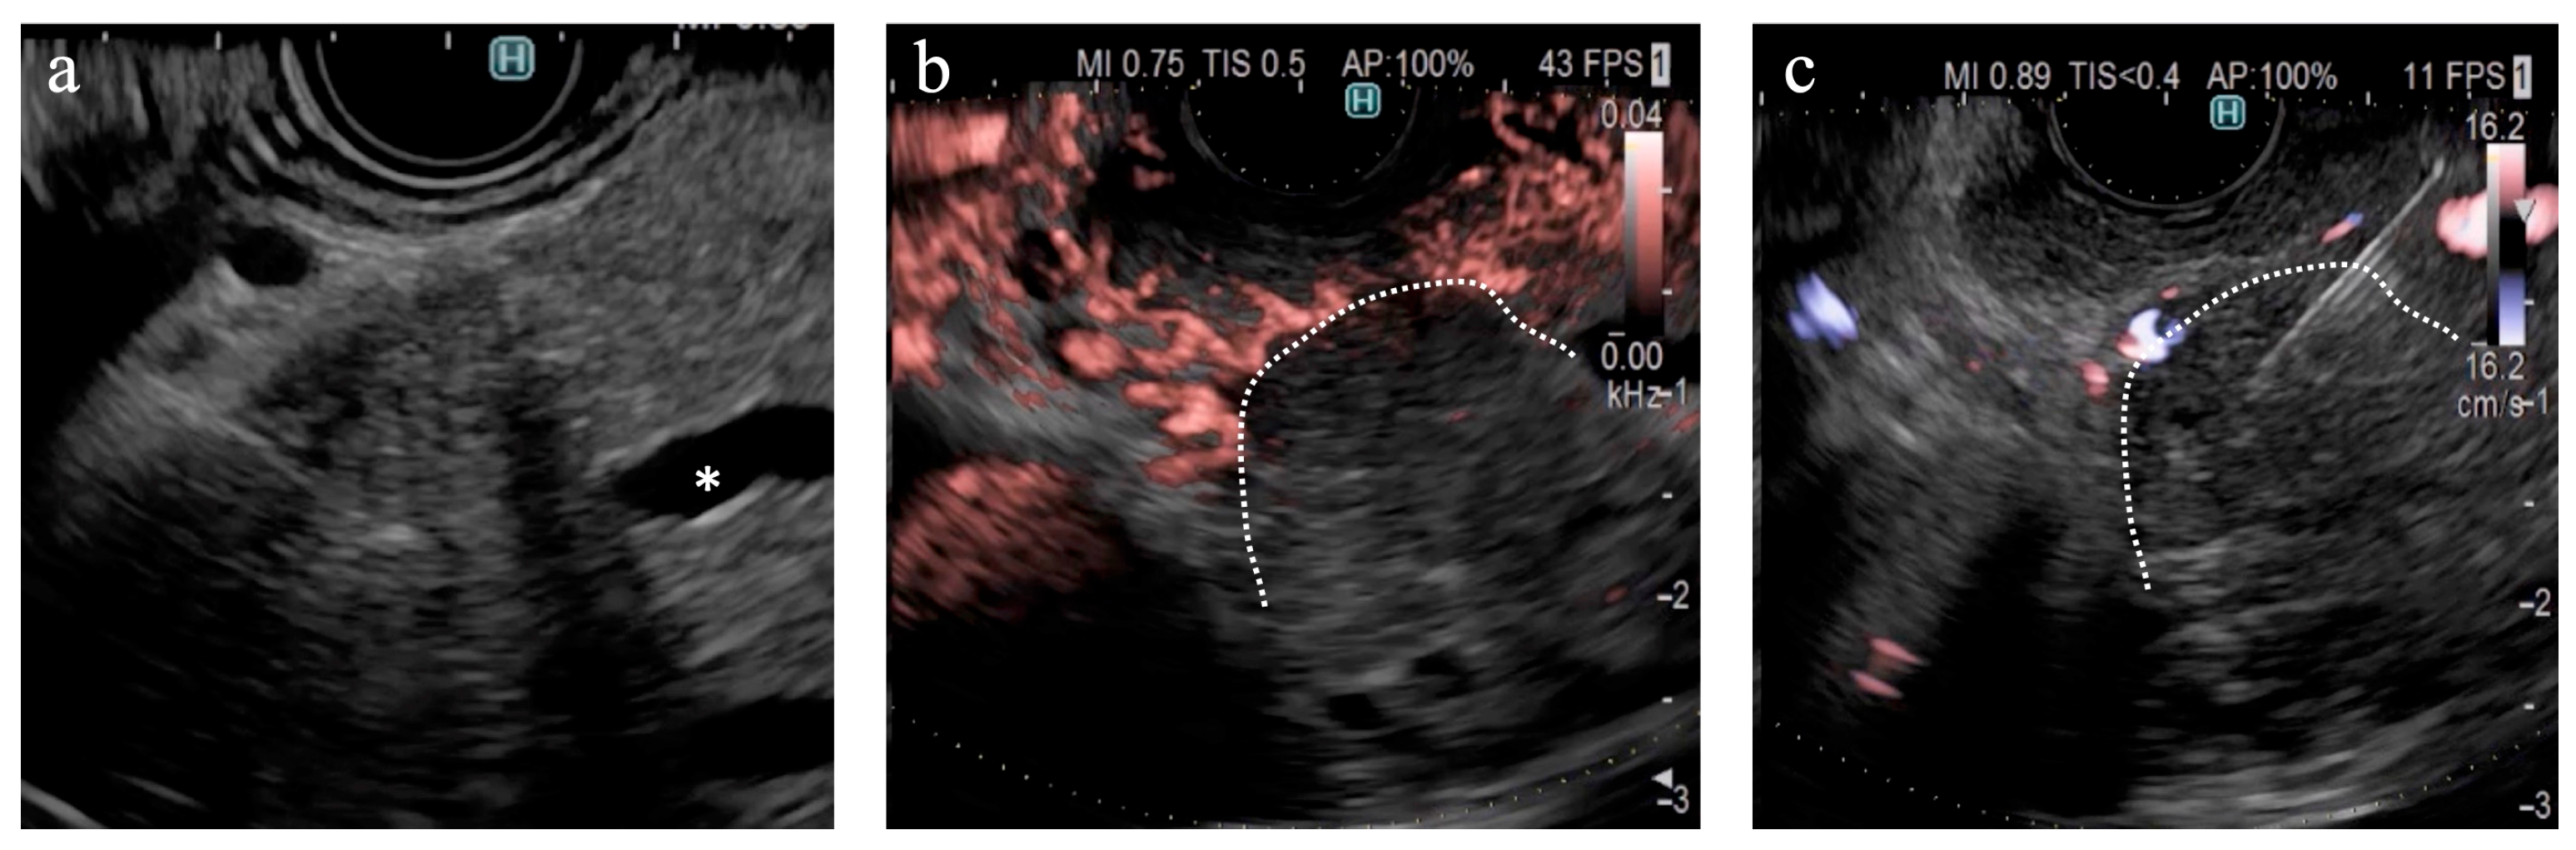

Figure 5. A case of pancreatic cancer (a) On B-mode, the main pancreatic duct is obstructed in the pancreatic head (*); however, the tumor margin is unclear. (b) On DFI, the tumor margin is detectable because of the interruption of vessels in the pancreatic parenchyma. (c) Endoscopic ultrasound-guided tissue acquisition was successfully performed according to the margin on DFI.